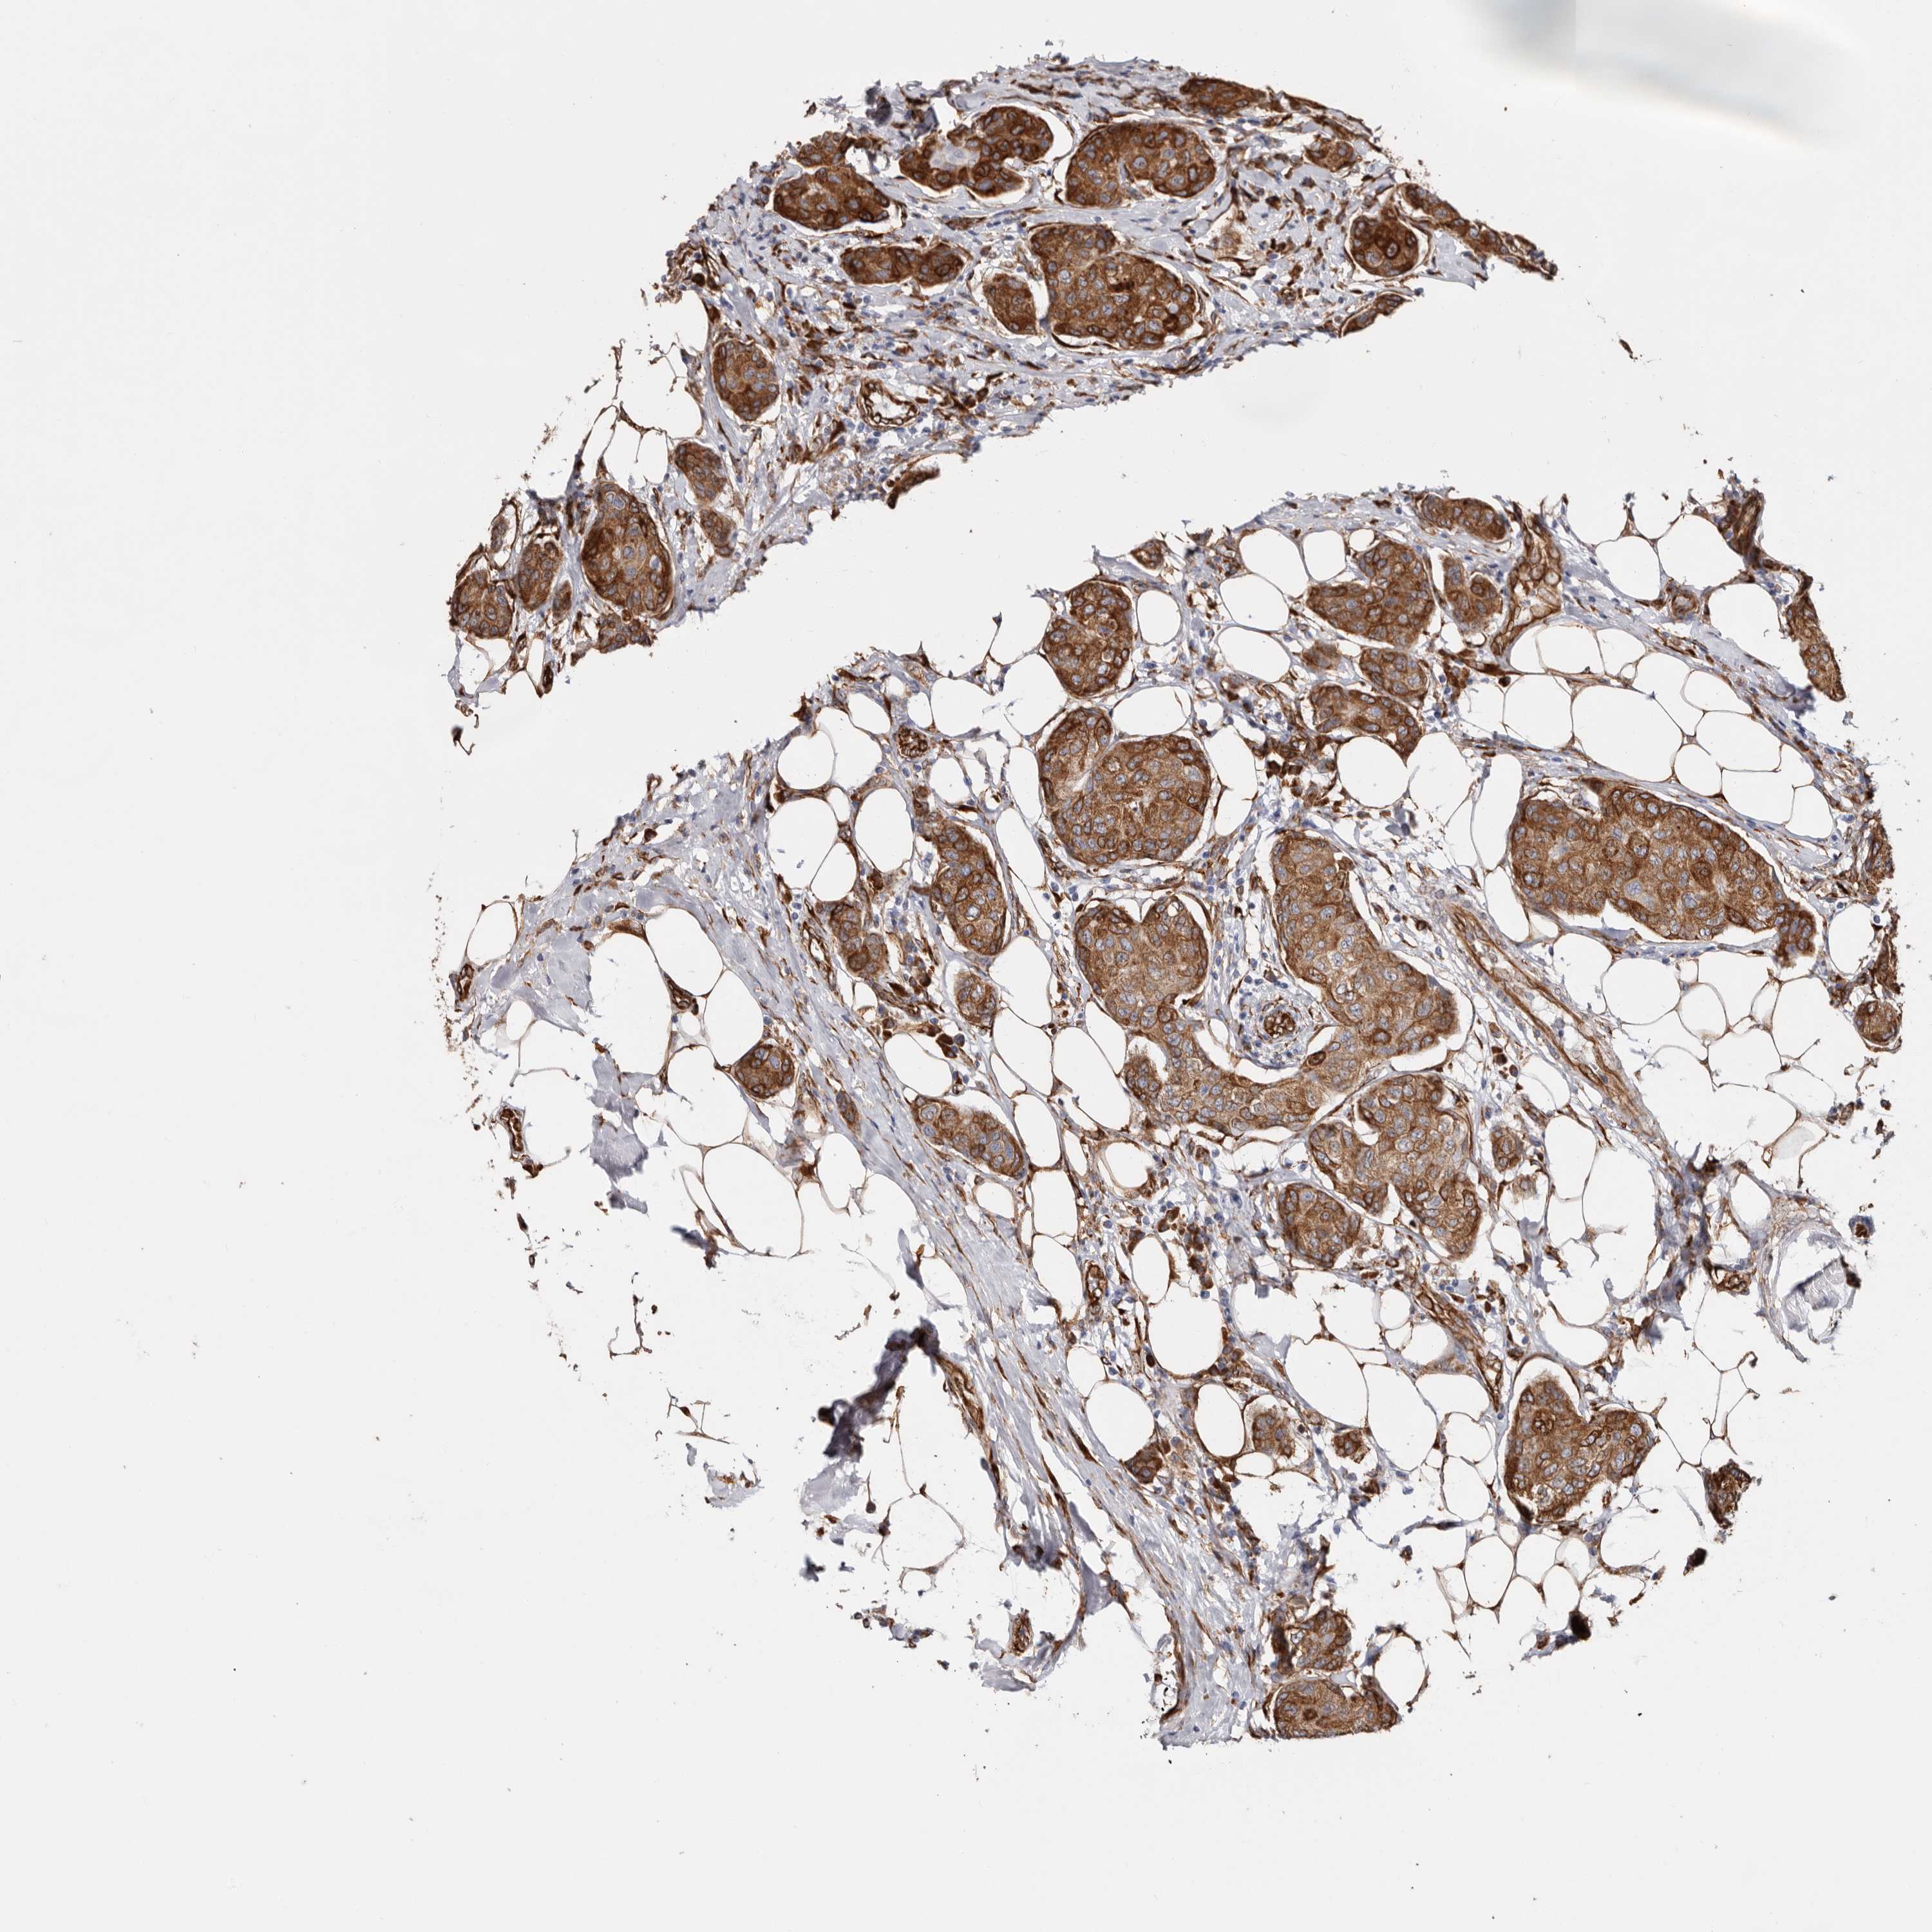

CANCER BREAST CANCER Show tissue menu

BRCA TCGA BRCA VALIDATION PROTEIN EXPRESSION